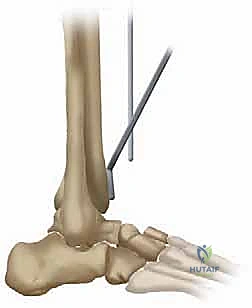

2. الشق الجراحي (المدخل الأمامي)

يقوم الدكتور هطيف، مستخدماً تقنيات الجراحة الدقيقة والميكروسكوبية عند الحاجة لحماية الأعصاب والأوعية الدموية، بعمل شق جراحي طولي في الجزء الأمامي من الكاحل. يتم إبعاد الأوتار والأعصاب (مثل العصب الشظوي العميق) بعناية فائقة للوصول إلى كبسولة المفصل.

3. إزالة الغضروف التالف وتشكيل العظام

باستخدام أدوات ومرشدات قطع (Cutting Jigs) متطورة جداً ومصممة خصيصاً لنظام TNK، وبمساعدة الأشعة السينية المباشرة في غرفة العمليات (Fluoroscopy)، يتم إزالة الأجزاء التالفة من أسفل عظم الظنبوب وأعلى عظم الكاحل (Talus). يتم إجراء هذه القطوعات العظمية بدقة مليمترية لضمان تطابق مثالي مع مكونات المفصل الصناعي.